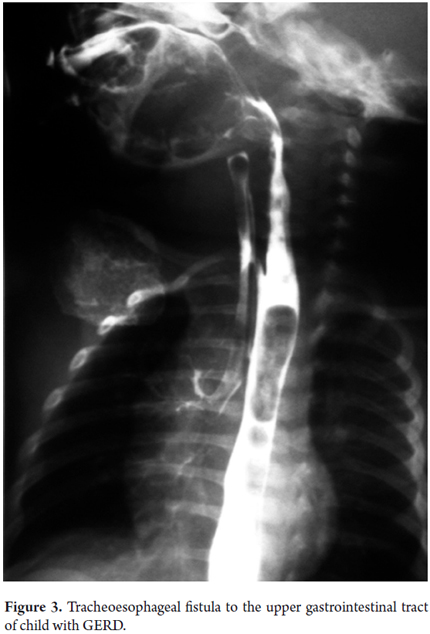

Sensitivity, specificity and reproducibility of some of the lab tests used to study children with GERD are displayed in Table 3 (19). To date, the gold standard for GERD diagnosis is the 24-hour ambulatory esophageal pH monitoring (21). This has now been complemented with impedance monitoring which allows more accurate diagnosis. It shows not only whether the reflux is acid or alkaline, but also shows the progression of reflux through the esophagus and whether there is any association between digestive and/or respiratory/otolaryngologic symptoms and esophageal pH changes. It reports four parameters including reflux rate (number of acid episodes/duration of procedure), number of acid episodes, number of acid episodes that last longer than five minutes, and duration of the longest episode. Results are considered abnormal if they are over percentile 50% of the reference tables for the patient's age (Figure 2). Today, placement of the Bravo endoscopic trans-catheter allows the study of children with a wireless 24-hour ambulatory esophageal pH monitor. Upper gastrointestinal tract scintigraphy can determine the reflux index (Normal is less than 4%), liquid gastric emptying (Normal is greater than 50%) and the presence of pulmonary microaspiration. Using a suction/swallowing mechanism when taking upper gastrointestinal images is an excellent method for detection of anatomical abnormalities such as strictures, fistulas, and hiatal hernias, but does not provide radiological diagnosis of GERD (Figure 3). Upper gastrointestinal endoscopy, besides visualizing esophageal motility and distension, can show possible anatomic abnormalities and the presence of macroscopic esophagitis. It also allows biopsies for determination of whether esophagitis caused by GERD or is eosinophilic or allergic (Figure 4). In search of improvements in the sensitivity of tests such as 24-hour esophageal pH tests and endoscopic diagnosis of esophagitis, we performed a study of 49 children aged 4 months to 13 years (mean age 5 years 4 months' ± 3 years 8 months) who had been diagnosed with GERD. Of these patients 26.5% had respiratory symptoms and 8.2% had digestive symptoms. We found no association between histopathological findings and results from the pH monitoring. Using bronchoalveolar lavage, siderophages carrying refluxed material towards the lungs have been identified. In more recent studies they have been shown to carry dipalmitoylphosphatidylcholine which is a major component of the surfactant (27). Even more recent studies have shown that the presence of bile acids and bronchoalveolar pepsin are associated with aspiration caused by GER in children with chronic lung disease (28). As described by Salazar et al., cineradiography and videofluoroscopy are dynamic examinations which make it possible to analyze the different phases of the sucking/swallowing mechanism in relation to different consistencies. In their study of 68 children between 1 month and 5 years old who had been diagnosed with swallowing disorders at the Hospital Universitario San Vicente de Paul in Medellin, Colombia showed that 84% presented gastrointestinal disturbances (mainly GER). Differential diagnoses of esophageal motility abnormalities were performed using manometry, and direct laryngoscopy identified otolaryngologic problems associated with GERD. Ultrasound is a noninvasive method which has increasingly become more important for diagnosis of GERD. Nevertheless, it requires an expert for its use and interpretation.